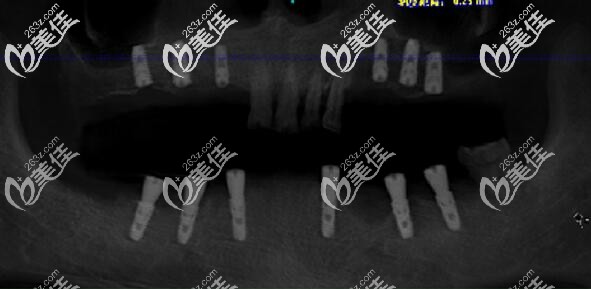

醫(yī)生介紹:馬建民,曾是醫(yī)院種植科主 任,現(xiàn)在是南京美奧口腔(鼓樓)院長,從事口腔臨床工作多年,擁有扎實(shí)的口腔基礎(chǔ)知識理論功底和豐富的實(shí)踐經(jīng)驗(yàn),擅長牙列缺損、牙列缺失的常規(guī)修復(fù)和種植義齒修復(fù),尤其擅長各種骨量不足條件下的種植治療。馬院長在種植方面的高超技術(shù),取決于他不懈的學(xué)習(xí)和鉆研,除了經(jīng)常參加種植新技術(shù)發(fā)布會(huì),國內(nèi)外口腔種植修復(fù)...